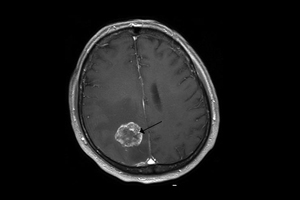

Novedades en detección, diagnóstico y tratamiento del cáncer

Con herramientas de boingeniería, biotecnología y bionformática